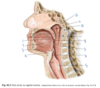

Which structure is labeled by #7?

Hypoglossal nerve (CN XII)

- Inferior to the lingual and glossopharyngeal nerves

- Lingual from CN V3, labeled #2 here

- Glossopharyngeal CN IX, labled #4 here

Which structure is labeled by #13?

Epiglottis

Which structure is labeled by #4?

Levator palati

Which structure is labeled by #6?

Eustachian tube

(Also #9)

Which structure is labeled by #6?

What is its action?

Recurrent laryngeal nerve

- Motor innervation to laryngeal muscles except cricothyroid muscle

- Visceral sensory below vocal cords

(Internal laryngeal nerve is visceral sensory above vocal cords, external laryngeal is motor to the cricothyroid muscle)